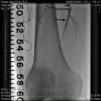

An angiogram from the left femoral sheath at this time showed retrograde filling of the distal and proximal SFA (Figure 4) and then the dissection plane in the EIA with a wire tip perforation and bleeding (Figures 5 and 6) to the retroperitoneal region at the external iliac artery with displaced bladder (Figure 6). Protamine was given to reverse the heparin and a 7-minute balloon inflation was performed in the distal SFA using a 5.0 mm×40 mm Evercross balloon (ev3, Plymouth, MN) to stop the retrograde bleeding. On repeat angiography, the distal SFA CTO was reoccluded and the dissection plane appeared to be sealed, with no further bleeding into the retroperitoneal region (Figures 7 and 8). Other than mild nausea after protamine, the patient reported no major symptoms during this procedure. When activated coagulation time was 130 s, the femoral and popliteal sheaths were removed. A 3-g/dl drop in hemoglobin was noted after the procedure that remained stable over the next two days. Popliteal and pedal pulses were palpable and unchanged following the procedure.